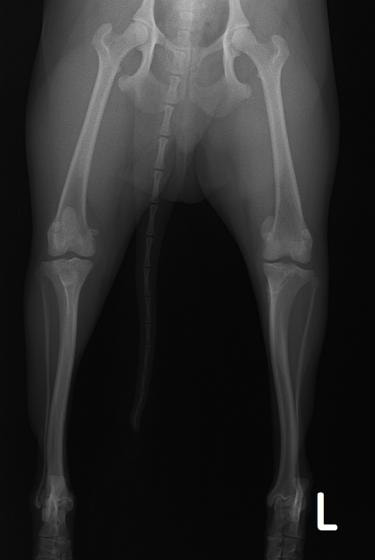

■ 症例20 ポメラニアン 8ヶ月 1.8kg

左右膝蓋骨脱臼 グレードⅢ

2ヶ月前から間欠的跛行が認められ、両膝の膝蓋骨脱臼整復術を行った。

手技は縫工筋及び内側広筋の解放、脛骨粗面の外側転位、滑車ブロック形造溝術、内外側関節包の縫縮を選択し実施した。

右側の膝蓋骨脱臼は上記手技で整復されたものの、左側はそれのみでは膝蓋骨が浮く様子が認められた。その為、PDS縫合糸にて膝蓋靱帯を1糸のみ縫合し、靱帯の縫縮を行った。

膝蓋骨脱臼は膝関節における膝蓋骨の内外側の脱臼と定義されるが、時として単純な内外の脱臼ではなく、膝蓋骨が大きく前方に浮き上がるように脱臼する場合がある。特にトイプードルやポメラニアンといった犬種に多く認められる。

内側脱臼に加えて前方への浮き上がりを矯正する為に、従来より脛骨粗面転移により膝蓋靭帯を外方と下方に引っ張り、固定する方法を選択する。膝蓋骨の前方への浮き上がりが軽度の場合は、従来法ではなく関節包の縫縮で対応していた。しかし、一部の症例で膝蓋骨の動きが悪くなり伸展機構が円滑に機能せずロボット様歩行になるケースがあった。

その為、膝蓋靭帯自体を縫縮する方法を採用した。この方法により、膝関節の伸展機構を妨げず膝蓋骨の軽度の浮きを矯正することが可能となった。

本症例の経過は良好である